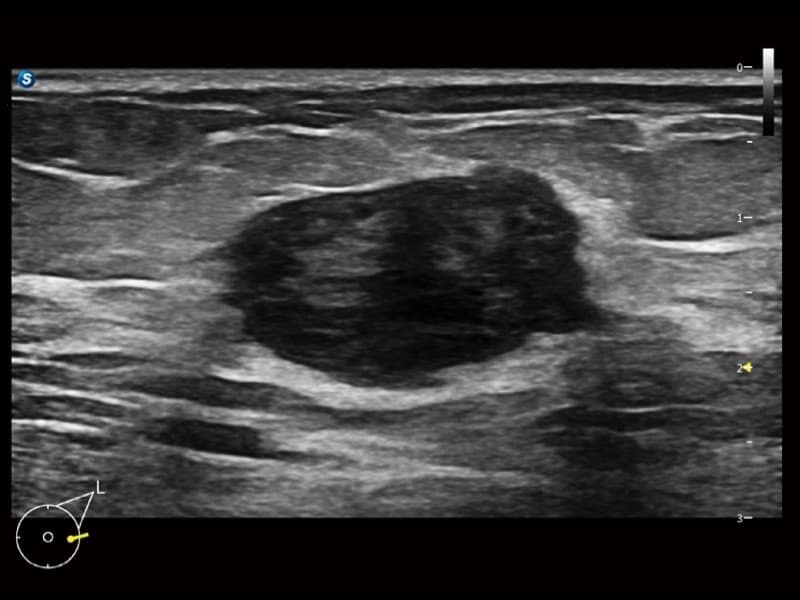

Klinische Bilder

- Radiologie: Quantitative Beurteilung der Lebersteatose durch ATI, Strain-Elastographie und kontrastverstärkter Ultraschall (CEUS)